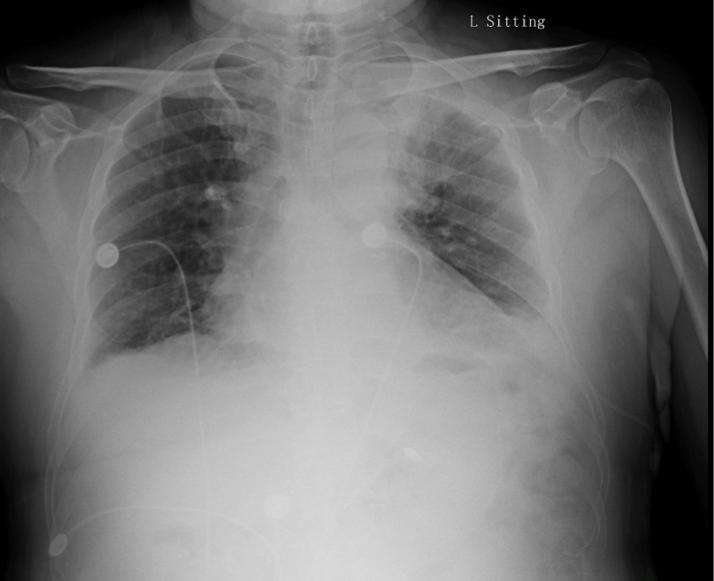

患者是在下午3点左右完成的手术,手术当天夜里10点出现了胸痛的症状,胸痛表现为与呼吸相关的刺痛。为患者完善了胸片,未见气胸,未见心包积液征象(图1)。这是典型的房颤患者围术期管理,因为进行了锁骨下静脉穿刺,因而需考虑到穿刺相关并发症的可能如气胸,但胸片无阳性发现,基本可除外。另外需要考虑到的致命并发症就是心包填塞,患者无心率快、血压低等典型表现,胸片未见心影增大,也不支持。

图1:患者开始出现胸痛,完善的胸片,未见气胸和心包积液表现,但回顾来看,左侧胸腔看似密度增高